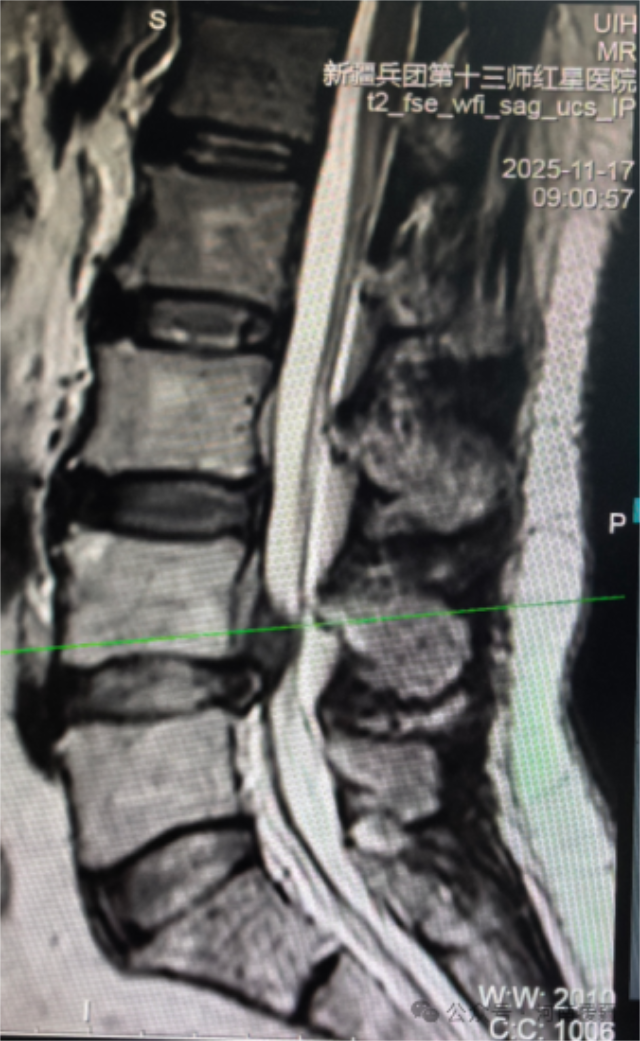

近日,新疆兵团第十三师红星医院神经外科与脊柱外科团队携手并肩,成功为腰椎间盘巨大脱出并游离的患者甄美丽(化名)实施单侧双通道内镜下腰椎间盘髓核摘除术(UBE)。这是全疆神经外科领域首次开展该手术,不仅实现了区域医疗技术 “零的突破”,更彰显了河南医疗援疆力量与本地医疗团队深度融合的丰硕成果,为边疆脊柱疾病患者带来了接轨国际的精准微创治疗新选择。

患者甄美丽的病情复杂棘手,巨大脱出并游离的腰椎间盘给治疗带来了极高挑战。医院对此高度重视,第一时间启动多学科协作(MDT)诊疗模式,神经外科与脊柱骨科核心成员迅速组建专项诊疗小组,召开多轮病例研讨会。为确保手术万无一失,医院特别邀请河南省人民医院脊柱脊髓外科高延征主任团队进行远程会诊,来自中原大地的顶尖专家团队凭借丰富的临床经验和深厚的学术积淀,为手术方案的优化提供了关键指导,与本地团队共同论证手术路径、细化操作流程,为手术安全实施筑牢了坚实的理论根基。